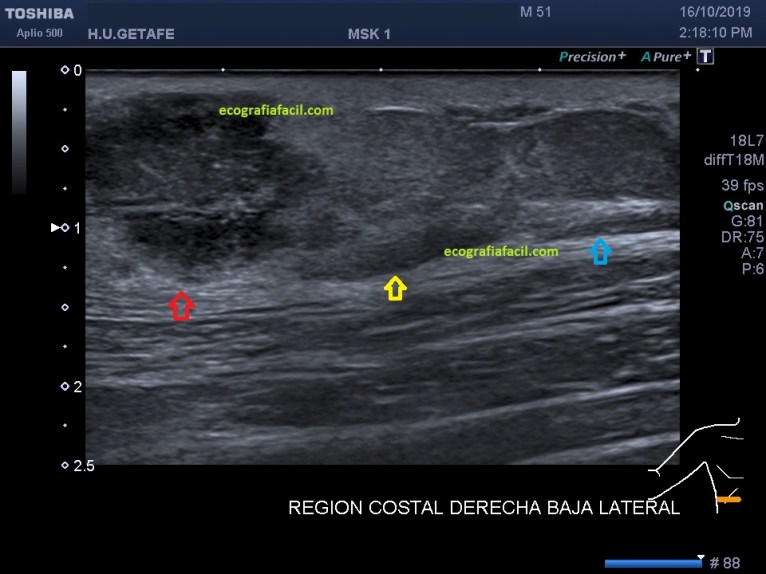

Lo primero que tenemos que tener claro es la anatomía. En la imagen «anatomía» te marco todo estratificado para que te des cuenta del nivel en el que se presenta la lesión que debemos estudiar, es importante que te fijes en la piel, si está respetada o no.

Después es muy importante que te fijes en el TCS, que es vital porque es donde se encuentra la lesión. Es una lesión que está dañando o infiltrando el TCS circundante, que está hiperecogénico en la imagen 4 y 5 puedes apreciar perfectamente las diferentes ecogenicidades semiológicas. La flecha amarilla marca la zona infiltrada del TCS y en azul celeste la ecoarquitectura preservada.

La LOE (lesión ocupante de espacio) es hipoecogénica, heterogénea, sólida, con bordes definidos, pero agrestes, aunque respeta tanto la piel como la fascia.

No es un absceso, porque es sólido, por eso el diagnóstico principal fue implante metastásico subcutáneo.